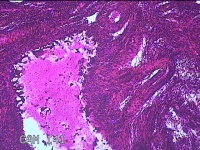

宫腔内容物

性别

女

年龄

48岁

临床诊断

宫腔占位

一般病史

发现宫腔占位1天。

标本名称

大体所见

灰白暗红色肿物2.2x1.3x0.2cm一个,表面糜烂,切开肿物呈实性,切面灰白暗红色,质软。